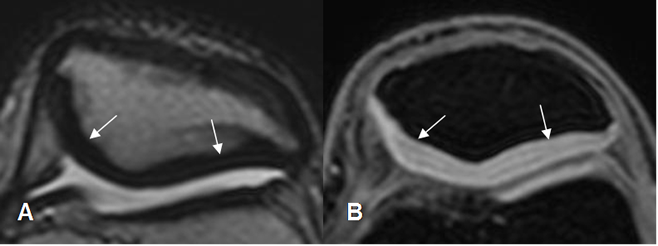

La patela es estabilizada por múltiples estructuras. En la parte superior por el tendón del cuadriceps, en la inferior por el tendón patelar, en la parte interna por el retináculo medial y vasto interno y en la externa, por el retináculo lateral, el vasto externo y la banda iliotibial. Los retináculo son estructuras hipointensas, que se insertan en los bordes de la patela y el fémur. (12). (Fig 33).

Fig 33. Retináculos normales.

A: RM axial 3D STIR en T1 y B: RM axial en T1. Retináculos normales hipointensos, entre la patelay el fémur. Medial (Flechas gruesas) y lateral (Flechas delgadas).

El cartílago articular es una estructura de bordes regulares y señal de intensidad (SI) homogénea, hipo o hiperintensa, según la secuencia elegida. (13). Las secuencias en T1 tienen buena sensibilidad para detectar lesiones condrales. (14).

Utilizando secuencias en T1 FS 3D FLASH, el cartílago muestra un aspecto trilaminar, con regiones superficial y profunda delgadas e hiperintensas y otra región media de señal intermedia. (15). (Fig 34 y 35).

Fig 35. Cartílago patelar normal.

A: RM axial en T2. Cartílago normal, con señal homogénea e hipointensa.

B: RM axial 3D en T1 STIR. Cartílago hiperintenso y de aspecto trilaminar.